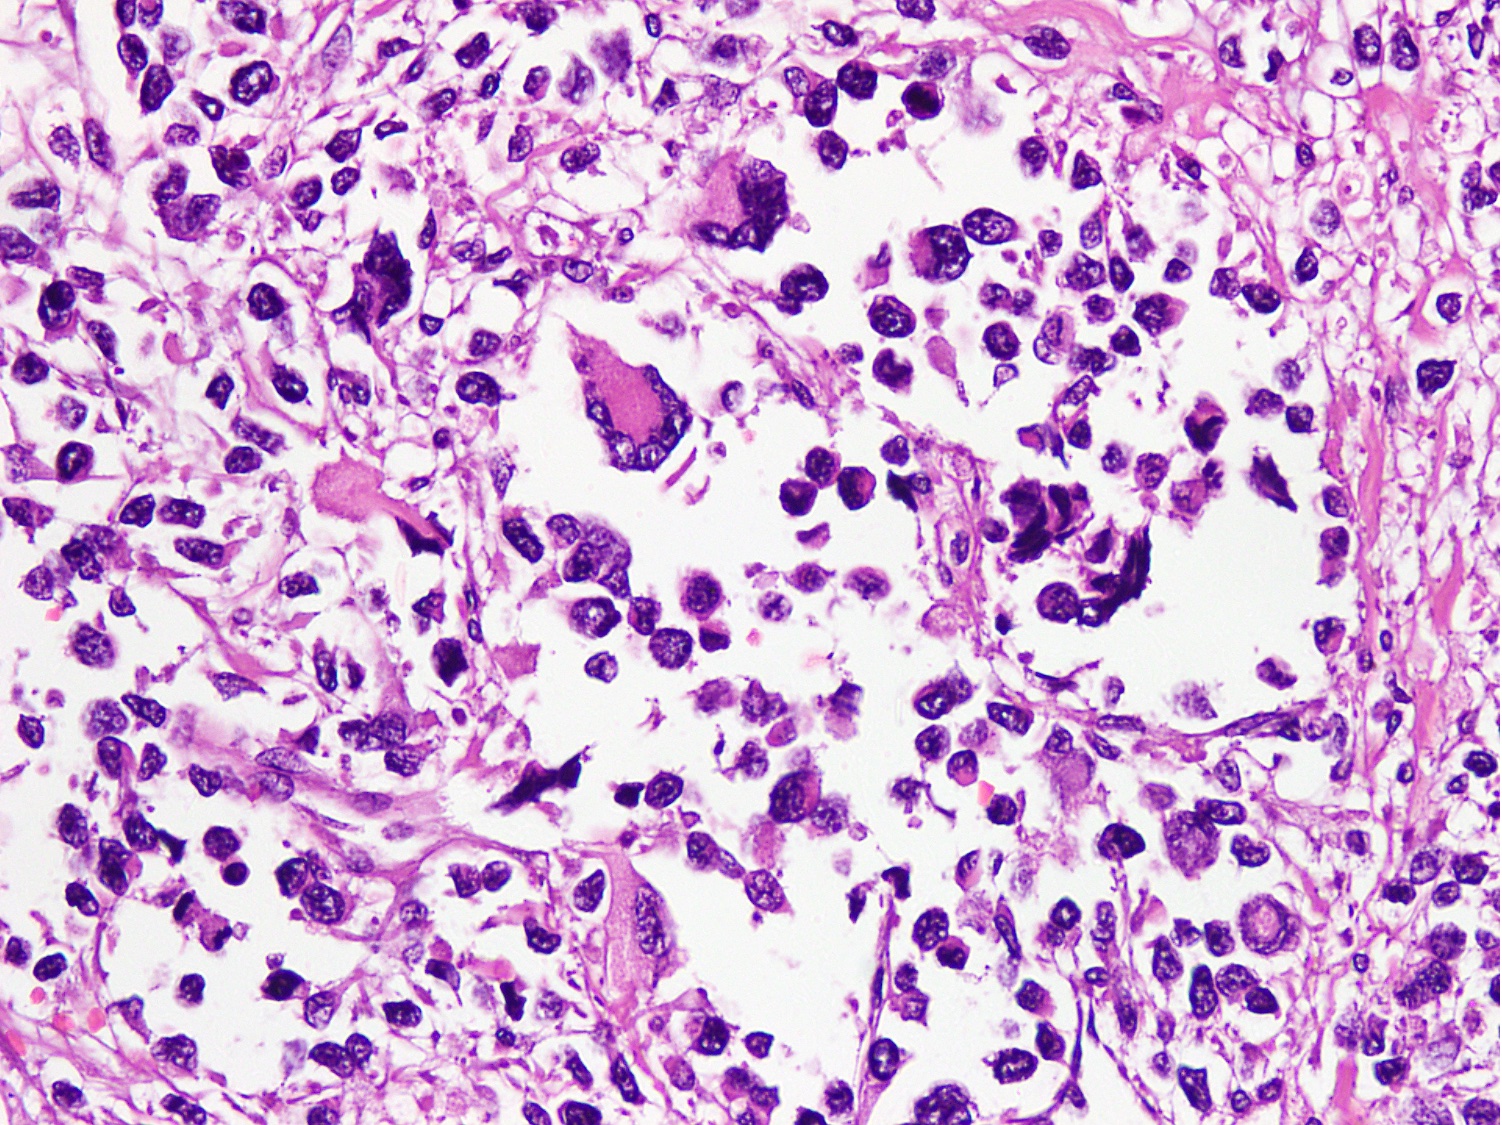

Microscopic (histologic) description

- Cellular round cell tumor

- Large clusters, nests, cords and trabeculae of primitive round cells, separated by variably thick fibrovascular septa

- Loss of cellular cohesion in the center forms alveolar-like, cystic and vague papillary appearance (Histopathology 2022;80:98)

- Layer of cells adheres to the periphery of the spaces and fibrous septa

- Small to intermediate sized monomorphic cells with scant cytoplasm

- Hyperchromatic nuclei with variable conspicuous small nucleoli

- Cells in the center have poor preservation and are necrotic; may appear floating

- Multinucleated tumor giant cells with wreath-like lineup of nuclei are common (Acta Pathol Microbiol Immunol Scand A 1982;90:345)

- Round to oval rhabdomyoblasts with abundant acidophilic cytoplasm may be present

- Brisk mitosis and variable tumor necrosis

- Occasional cases may show clear cell morphology with pale, glycogenated cytoplasm

- Rare anaplasia

- Some cases may show histologic features of embryonal rhabdomyosarcoma; molecular studies are essential to characterize such cases (Am J Clin Pathol 2013;140:82)

- Solid variant:

- Sheets of neoplastic cells

- Lack fibrovascular septa, pseudoalveolar spaces and dyscohesion (Cancer Genet Cytogenet 2005;163:138)

- May show rhabdomyoblastic differentiation

- Abundant mitotic activity

Microscopic (histologic) images

Contributed by Nasir Ud Din, M.B.B.S.